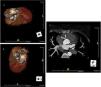

She underwent coronary angiography (CA) during which selective cannulation of the left coronary artery (LCA) was not possible, and a non-selective injection disclosed no coronary artery arising from the left coronary sinus. On selective injection of the right coronary sinus, a single ostium was visualized. The right coronary artery (RCA) was a great vessel, with no stenosis. A hypoplastic left anterior descending artery (LAD) and left circumflex artery (LCx) were perfused from RCA collateral vessels, both without lesions (Figure 2). Left ventriculography revealed apical ballooning akinesis, basal hyperkinesis and severe LV dysfunction (Figure 3).

Coronary computed tomography angiography (CCTA) revealed a single coronary artery with its ostium in the right sinus of Valsalva (RSV), agenesis of the left main artery and a hypoplastic LAD, the RCA with a normal course, antegrade flow through a posterior lateral branch (PLB) to the LCx and LAD, and collaterals originating from the posterior descending artery (PDA) to the distal segment of the LAD. All coronary arteries were patent and with no evidence of atherosclerotic plaque (Figure 4).

Figure 4.

Coronary computed tomography angiography depicting a single coronary artery with its ostium in the right sinus of Valsalva (arrow), agenesis of left main artery and hypoplastic left anterior descending artery; right coronary artery with a normal course. All coronary arteries were patent with no evidence of atherosclerotic plaque.